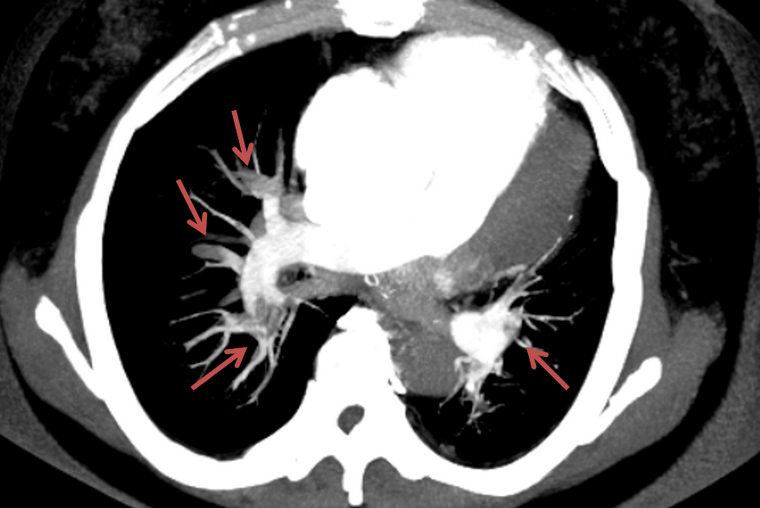

近日,韩女士在一次户外活动中,突然晕倒在地,失去意识,被立即送往郑州大学五附院急诊科抢救。苏醒后的韩女士虽然生命体征平稳,但出现了胸闷、心悸等不适症状,经肺动脉CTA检查后(图1),她被诊断为肺栓塞,同时下肢彩超发现右侧下肢腘静脉有漂浮血栓,双侧肌间静脉多发血栓,原来导致韩女士发病的罪魁祸首是下肢深静脉血栓。经血管外科给予下腔静脉滤器植入拦截血栓(图2)及抗凝治疗后,有效遏制血栓进一步发展,及时控制了病情,目前已转危为安。

▲ 图1:肺栓塞